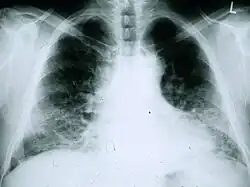

As radiografias de tórax são úteis na rotina de acompanhamento de pacientes com FPI. Infelizmente, as radiografias simples de tórax não são diagnósticas, mas podem revelar volumes pulmonares reduzidos, geralmente com marcas intersticiais reticulares proeminentes próximas às bases pulmonares.[3]

A avaliação radiológica por meio da TCAR é um ponto essencial no caminho do diagnóstico da FPI. A TCAR é realizada usando um scanner tomográfico axial computadorizado convencional sem injeção de agentes de contraste. As fatias de avaliação são muito finas, de 1 a 2 mm.

A TCAR típica do tórax da FPI demonstra alterações fibróticas em ambos os pulmões, com predileção pelas bases e pela periferia. De acordo com as diretrizes conjuntas das ATS, ERS, JRS e ALAT de 2011, a TCAR é um componente essencial da via diagnóstica na FPI, que pode identificar a PIU pela presença de:[3]

- Opacidades reticulares, geralmente associadas a bronquiectasias de tração

- Favos de mel manifestados como espaços aéreos císticos agrupados, geralmente de diâmetros comparáveis (3-10 mm), mas ocasionalmente grandes. Geralmente são subpleurais e caracterizados por paredes bem definidas e dispostos em pelo menos duas linhas. Em geral, uma linha de cistos não é suficiente para definir os favos de mel.

- Opacidades de vidro fosco são comuns, mas menos extensas do que a reticulação.

- Distribuição caracteristicamente basal e periférica, embora muitas vezes irregular.

Tomografia computadorizada de alta resolução do tórax de um paciente com FPI. As principais características são um padrão periférico, predominantemente basal, de reticulação grosseira com favos de mel